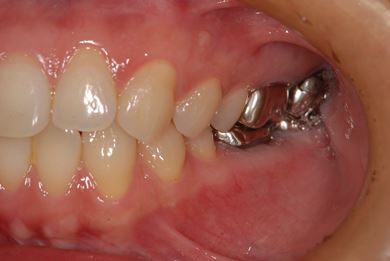

| 性別/年齢 | 女性 / 39歳 | ||||||||||||||||||||||||||||||||

| 主訴 | 右奥歯の虫歯と、右奥のインプラント治療について相談。 | ||||||||||||||||||||||||||||||||

| 治療方針 | 右下奥欠損部分をインプラント治療にて、機能的・審美的回復を行う。 | ||||||||||||||||||||||||||||||||

| 治療内容 | インプラント1本、ハイブリッドセラミッククラウン1本 | ||||||||||||||||||||||||||||||||

| 総治療費 | 329,963円 | ||||||||||||||||||||||||||||||||

| 治療期間 | 5ヶ月 |